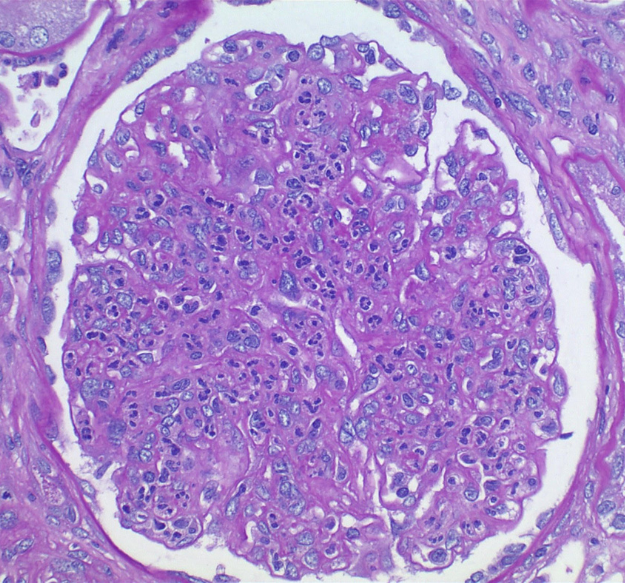

Diabetic kidney disease (DKD), also known as diabetic nephropathy, is a condition where the high blood sugar levels cause damage to the filtering system of the kidneys. High blood pressure can cause further kidney damage. This condition can be detected early by checking for urine protein leak, as only after 50% of the kidneys is damaged before the kidney function test is abnormal.